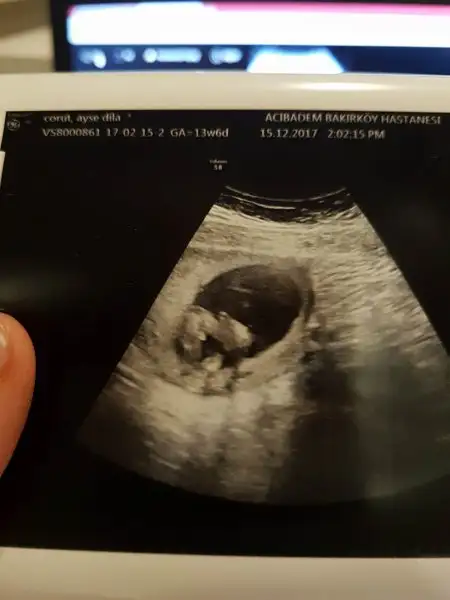

Gittik canim iyiyiz cok sukur basta kiz dedi sonra erkek bu dedi cikinti var ama odemde olabilir dedi ben saskin kaldim 16. Haftada netlesir dedi resmi yukliycemGittin mi canım dokt. iyisiniz inş.

Gittik canim iyiyiz cok sukur basta kiz dedi sonra erkek bu dedi cikinti var ama odemde olabilir dedi ben saskin kaldim 16. Haftada netlesir dedi resmi yukliycem

Odem degilse bildigin pipi var bacak arasi ultrasonu:))İyi olmanıza sevindim canımama bu sipa belli edemedi kendini benim içimden kız geçti ama canım